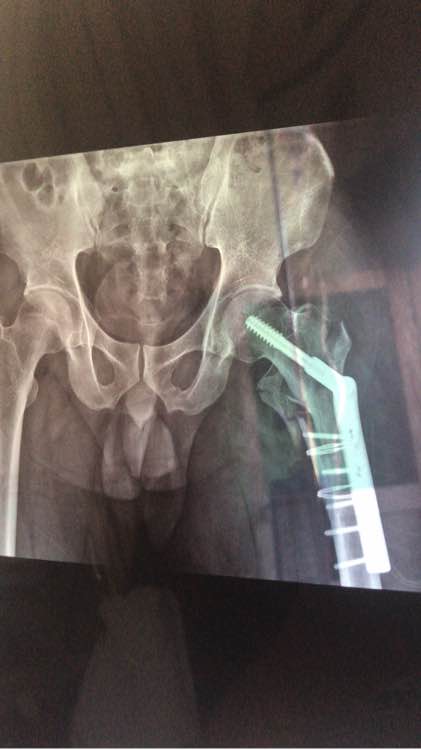

术后3天片子,术前的片子好像丢了

拍完片后,确定大腿骨折(后面附图),然后办理入院手续。终于能够躺下不用动了,心里稍微觉得舒服了一点。在床上躺了2个多小时终于见着医生了,第一句就问我哪里不舒服,我说除了大腿不舒服,其他地方都挺好的……然后他说要做手术哦,我忐忑的问了一句什么时候做,然后他过来摸了一下我大腿,说,先观察几天,估计下周一消肿了才能做。